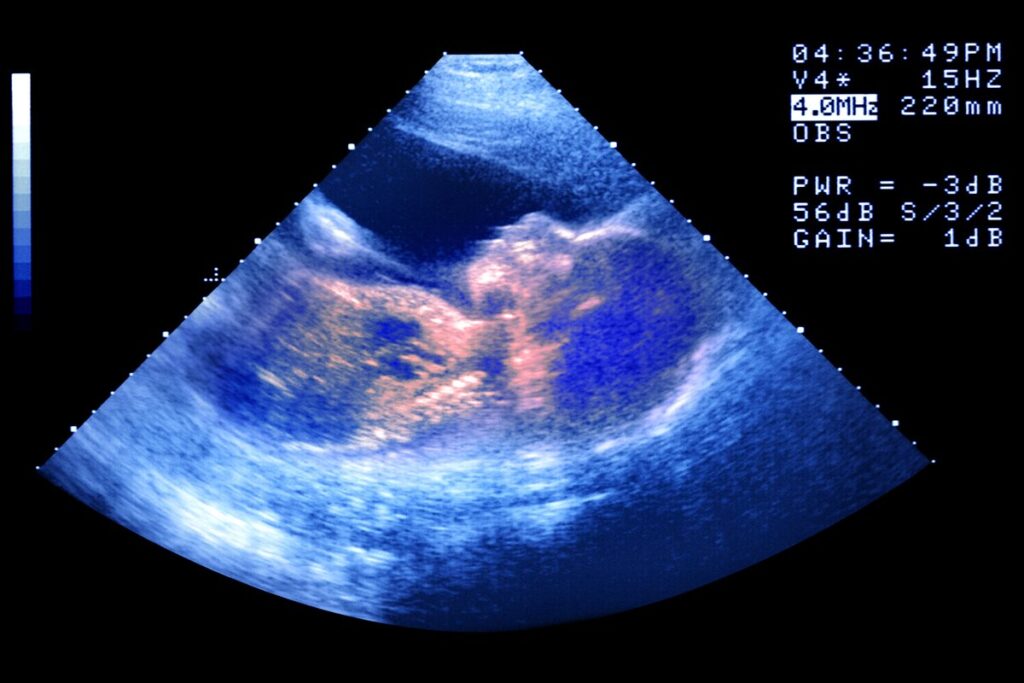

A fertilização in vitro (FIV) é a técnica mais popular de reprodução assistida